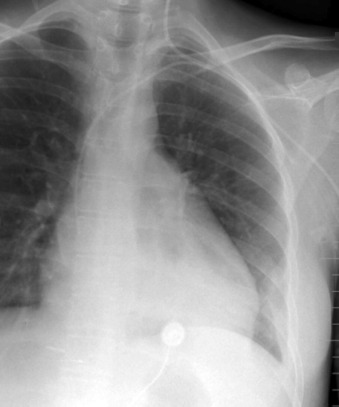

Central Venous Lines ( Figs. 22-1 to 22-13 )

To avoid mechanical irritation (from the catheter tip) and chemical irritation (from infusate) of the right atrium, the catheter tip of a central venous line should be further than the junction of the internal jugular vein and subclavian veins (near the level of the first thoracic rib). In addition, the tip should not be further in than the junction of the superior vena cava and right atrium. Central venous catheters that are intended to record central venous pressure should lie distal to the last venous valves (in the subclavian and internal jugular veins, 2.5 cm proximal to the beginning of the brachiocephalic vein) and before the right atrium. The ideal position of the tip of a peripherally inserted central catheter (PICC) line is in the distal superior vena cava.